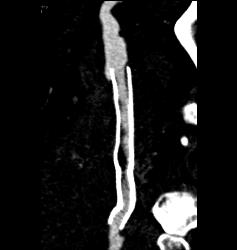

Peripheral Vascular Disease (PVD) With Stent Grafts